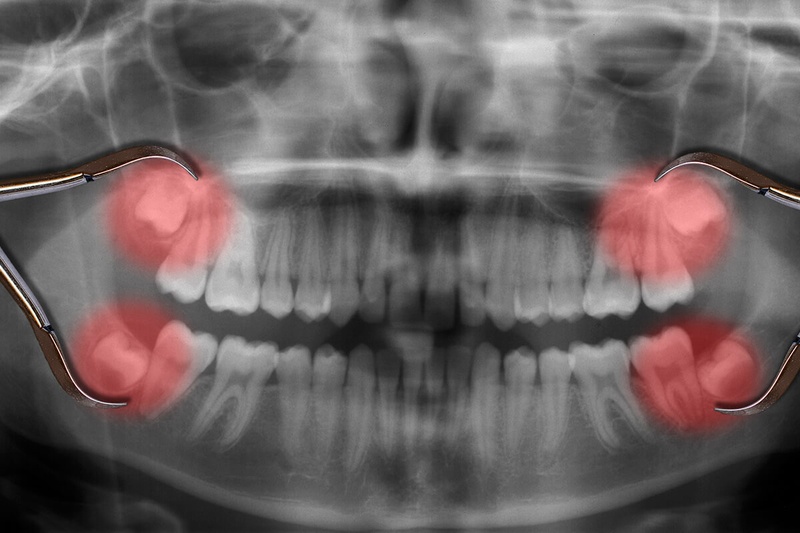

Răng khôn hay còn gọi là răng số 8, thường gây ra nhiều phiền toái khi chúng có biểu hiện mọc ngầm, mọc lệch. Quyết định có nên nhổ răng khôn mọc lệch không, thường phụ thuộc vào chỉ định của bác sĩ sau khi thăm khám và chụp X-quang trong các trường hợp sau:

Mức độ phức tạp của một ca tiểu phẫu phụ thuộc lớn vào hướng mọc của răng. Thông qua phim X- quang, bác sĩ sẽ xác định kiểu răng khôn mọc mà bệnh nhân đang gặp phải. Mỗi kiểu mọc sẽ có những nguy cơ tiềm ẩn khác nhau, cụ thể: